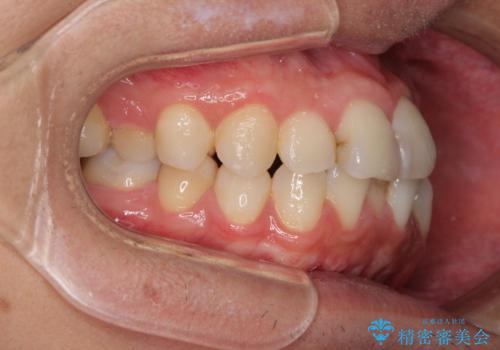

顎が左右にずれた咬み合わせ ハーフリンガルの抜歯矯正

- 30代男性

- 口元の突出感を気にして来院された患者様です。

目立たない装置を希望され、上顎が裏側装置で下顎が表側装置のハーフリンガルを希望されました。

上下の顎骨が左右に大きくずれており、奥歯が交叉咬合となっていたため、ハーフリンガルよりも表側装置をおすすめしましたが、目立たない装置を強く希望されたため、治療期間が長期化することを前提に、ハーフリンガルにて抜歯矯正を行うこととしました。